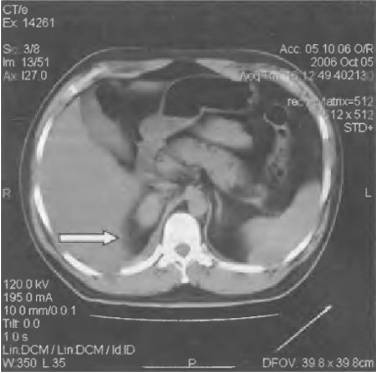

Диагностировать заболевание можно при помощи анализа крови, УЗИ почек, экскреторной урографии, КТ и МРТ.

Среди инструментальных диагностических методов используют УЗИ органов системы мочевыделения, экскреторную урографию, радиоизотопную ренографию, КТ и биопсию почек.